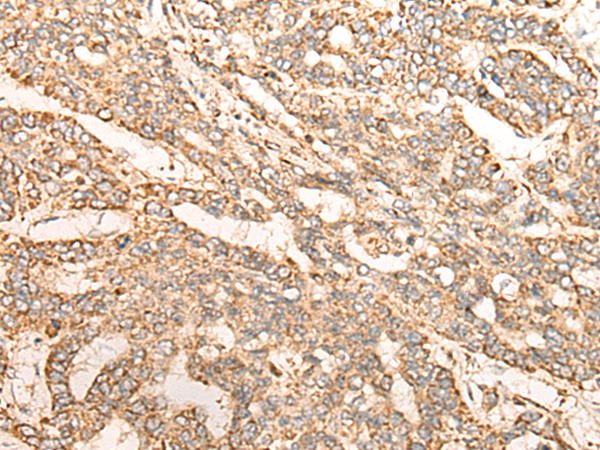

分类: 科研抗体货号: P09404别名: RESA1; SELRC1; C1orf163应用: WB,IHC反应种属: Human, Mouse